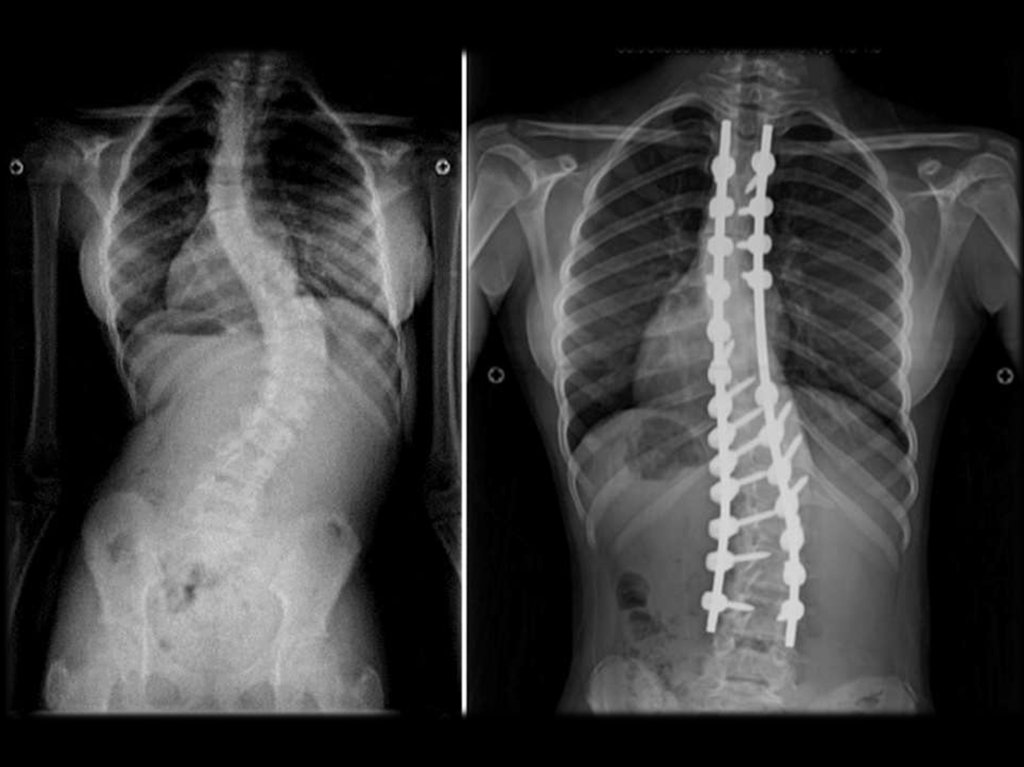

СКОЛЕОЗ ГРУДНОГО ОТДЕЛА

21.